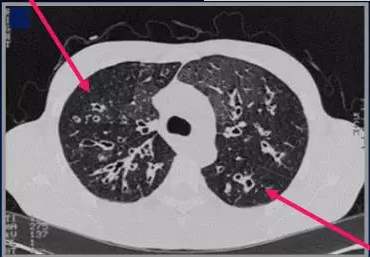

囊性纤维化(Cystic Fibrosis,CF)是一种具有家族常染色体隐性遗传性的先天性疾病,主要影响肺(CPF),肺囊性纤维化(Pulmonary Cystic Fibrosis,CPF)是造成80%的囊性纤维化患者死亡的原因。囊性纤维化也影响胰腺,肝,肾和肠。作为一种外分泌腺的病变,胃肠道和呼吸道常累及,由于支气管中的黏液增多,可使支气管阻塞,使某些细菌(如金黄色葡萄球菌、铜绿假单胞菌等)易于生长繁殖,进一步引起肺、支气管的反复感染,继之引起肺囊性纤维化(特征性纤维化和形成囊肿)。